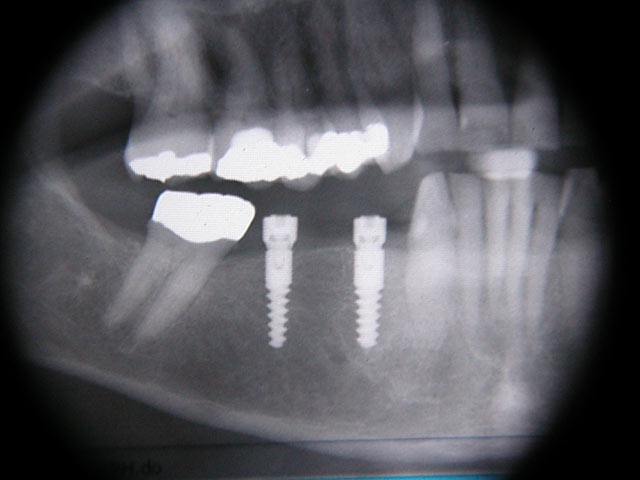

Implantation mit fester Brücke: